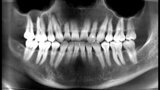

Treatment of the result of chronic activation of substance P